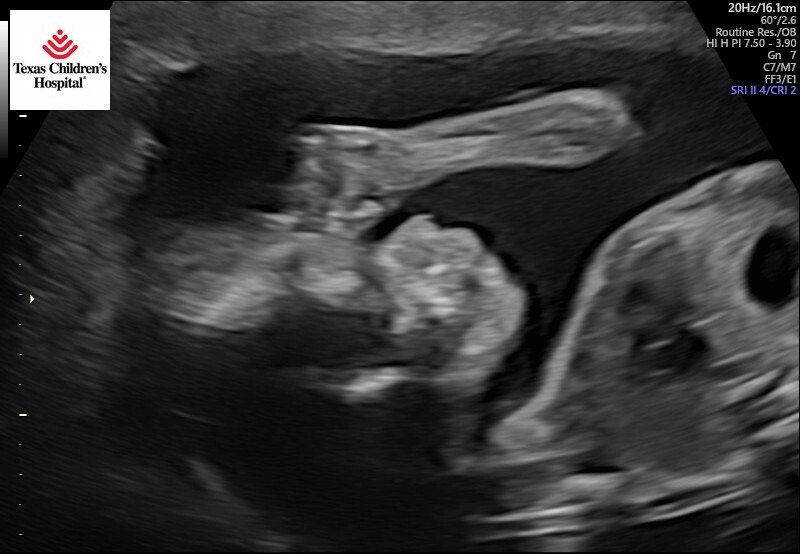

If you have hung with me this long – WOW, Bless you. I’ll get to the good stuff with my 20-week anatomy scan. It was this past Monday, December 9th. Mom and Dad flew in Sunday night to go with me to that visit, and I aligned my OB visit that same day so they could meet her and see the hospital I would deliver.

Oliver’s anatomy scan was perfect for 20 weeks was perfect– all systems and organs are working and healthy. This I DO NOT TAKE FOR GRANTED! I am so grateful. And so excited. My parents being here for the day to see this hour long view of Oliver was sweet. We praised God for the journey, and His protection over me and Oliver. My faith-compass tells me He’ll walk us through the next 4 months.